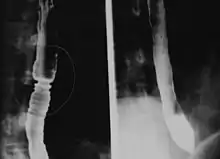

La radiografía tras la ingesta de papilla de bario muestra múltiples anillos asociados con la esofagitis eosinofílica.

Estrechamiento del esófago que suele producir impactación alimentaria, disfagia y reflujo. Los niños pequeños con esofagitis eosinofílica pueden tener dificultad para comer, dolor abdominal o vómito. Es más común en hombres, y afecta tanto a adultos como a niños.[1]